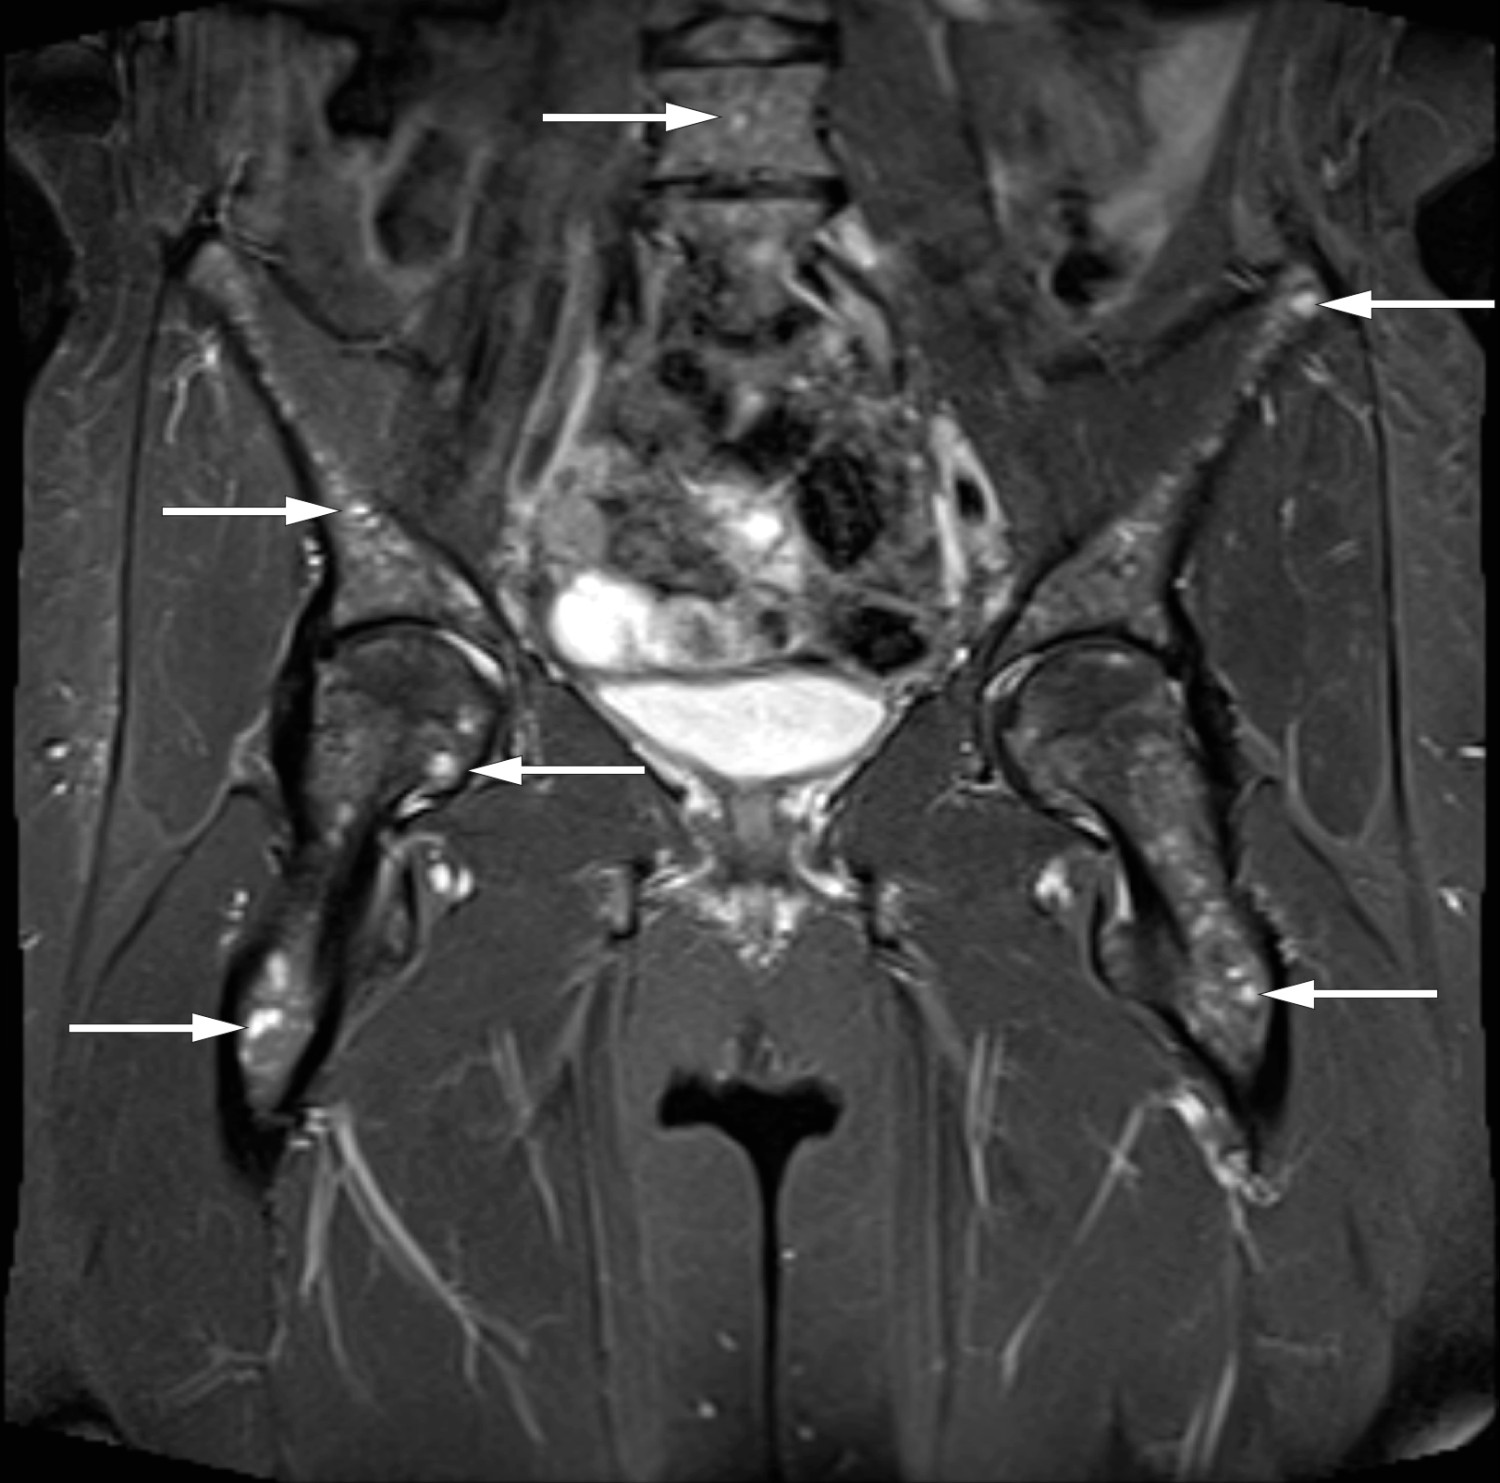

Pasienten var en kvinne i 40-årene med hypertensjon og psoriasis. Hun hadde gjennomgått en langsgående ventrikkelreseksjon (gastric sleeve) og var utredet for mangeårige smerter i nedre del av rygg, med funn av prolaps i lumbosakralcolumna på MR to år tidligere. De siste månedene hadde pasienten hatt økende smerter og ubehag i bekkenet med bilateral utstråling til underekstremitetene. Smertene var ilende og av en annen karakter enn de hun kjente fra sin prolaps. De økte ved belastning, men var også til stede i hvile. Fastlegen hadde tolket symptomene som relatert til prolapsen og hadde henvist pasienten til behandling hos fysioterapeut samt anbefalt smertelindring med NSAID-preparater og opiater. Pasienten hadde en fysisk krevende jobb og var nå sykmeldt på grunn av det aktuelle. Som ledd i utredningen hos fastlegen var det gjort ny MR-undersøkelse av bekken og lumbosakralcolumna. Den viste småflekket signalforandring i beinmarg, mest uttalt i bekkenringen og hofteregionen (figur 1).

Den aktuelle pasienten hadde ryggsmerter av ny og annen karakter enn hun tidligere hadde hatt, uten bedring av konservativ behandling. Det ble funnet indikasjon for bildediagnostikk for å utelukke underliggende sykdom. MR avbilder beinmargens bløtdelskomponent direkte og er sensitiv for påvisning av patologiske prosesser i skjelettet (5). Infiltrasjon i beinmarg ved MR er et lite spesifikt funn som ses ved flere tilstander i skjelettet (4). Et histologisk bilde med ikke-nekrotiserende granulomer, som hos vår pasient, kan forekomme ved sarkoidose, malignitet og infeksjoner (10). Diagnosen sarkoidose sikres ved biopsi (11), og det er foreslått kliniske diagnosekriterier for sarkoidose ramme 1) ((11).

Sarkoidose er en systemisk inflammatorisk sykdom av ukjent etiologi, karakterisert av patologisk granulomdanning i affiserte organ (2, 8, 11). Patogenesen er bare delvis kartlagt (12, 13). Lungene angripes oftest, og mer enn 90 % har lungeforandring (7). Beinmargsaffeksjon er sjelden, både som isolert manifestasjon eller som ledd i mer utbredt sykdom (14, 15). En studie fra 2014 viste at i gruppen med beinmargsaffeksjon hadde 90 % affisert bekken og lumbosakralcolumna (16). Sarkoidose i beinmarg forekommer som oftest uten hematologiske avvik (17), som hos vår pasient. Smerter relatert til beinmargsaffeksjon av sarkoidose kan forekomme ved aktiv sykdom (15). Symptomatisk effekt av behandling av sarkoidose i beinmarg er ikke godt dokumentert, og prognosen avhenger av utbredelse av sykdom og grad av organpåvirkning (16, 18, 19). Kortikosteroider vil vanligvis være førstevalg dersom behandlingsindikasjon for sarkoidose foreligger.